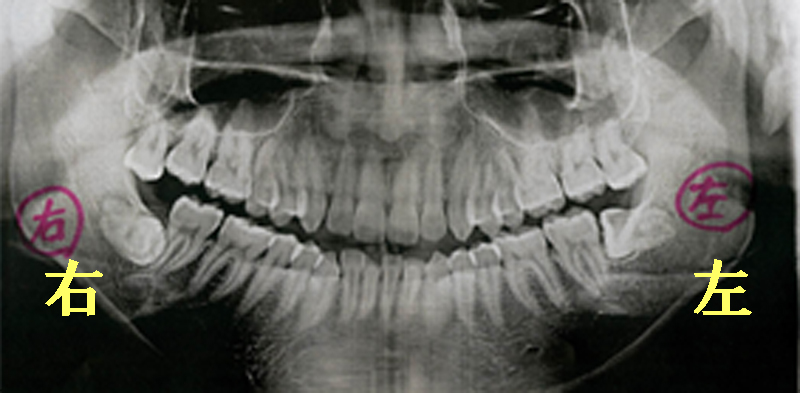

レントゲン写真で見る親知らずの症例

さあ、ではこのレントゲン写真では何が起こっているのみてみましょう。

右下の一番奥に斜めに生えている歯がありますね。これが親知らずなんです。

親しらずは矢印の方向に隣の歯たちをエイッエイッと押し続けているんです。

親しらずが矢印方向手前に歯を押す力により隣の歯が下から上に突き上げられているのがわかります。

歯っていうのは頭でっかちの形態なんですね。

頭でっかちなので歯の頭部分に引っかかって上に押し上げられてしまうんです。

かみ合う上の歯はもう抜けてなくなっているため押し上げられた歯はどんどんどんどんさらに押し上げられます。

上に押し上げられた隣の歯たちはドミノ倒しのように横へ横へと前方へ前方へ倒れ続けていきます。

この押す力は実はずっと続きます。

わずかな力でも押し続けることにより歯並びはどんどん崩れます。

怖いですよね。

歯は一生動き続けるものだからです。